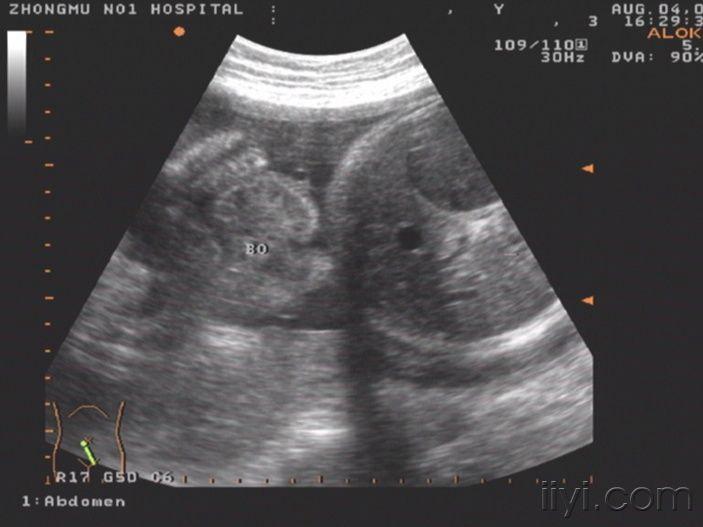

你见过这么大的胎儿胃泡吗你考虑什么畸形

36w胎儿,胃泡是不是有点大?有意义吗?

36w胎儿胃泡是不是有点大有意义吗